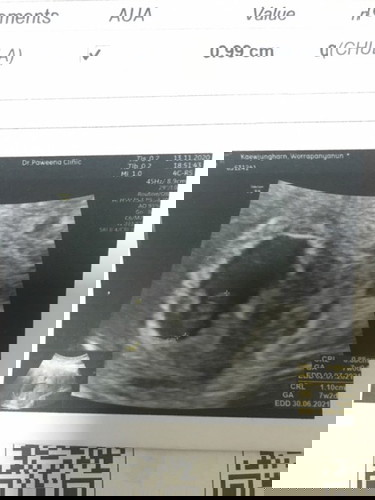

ตั้งท้อง ท้องอ่อนๆอยู่

คุณแม่เครียด ตอนนี้ตั้งท้อง9สัปดาห์ ดีใจมากอย่างน้อยก็มีสิ่งที่สำคัญในตัวเรา แต่แฟนหาว่าเรามีคนอื่นใส่ร้ายเรา แม่ก็เลยเครียดค่ะ